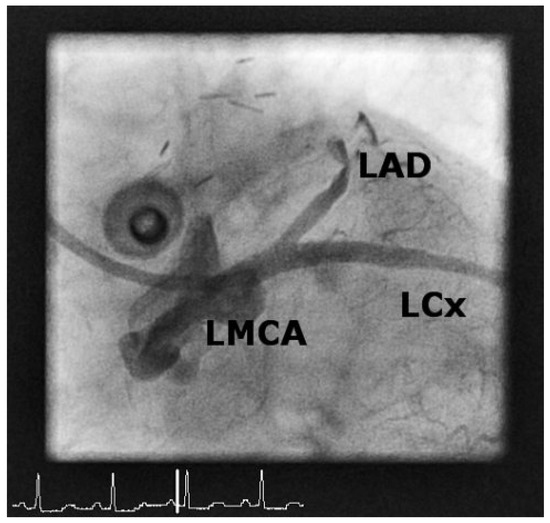

Iatrogenic Left Main Stem Stenosis After Surgical Aortic Valve Replacement

by Jens Robert, David Tüller and Stephan Windecker

Cardiovasc. Med. 2011, 14(3), 101; https://doi.org/10.4414/cvm.2011.01578 - 23 Mar 2011

Surgical aortic valve replacement (SAVR) represents the gold standard in the treatment of symptomatic severe aortic valve stenosis as reflected by the class I indication assigned in the ACC/AHA and ESC guidelines. SAVR effectively relieves symptoms, improves quality of life as well as [...] Read more.

Surgical aortic valve replacement (SAVR) represents the gold standard in the treatment of symptomatic severe aortic valve stenosis as reflected by the class I indication assigned in the ACC/AHA and ESC guidelines. SAVR effectively relieves symptoms, improves quality of life as well as prognosis of affected patients. As with any therapeutic intervention, SAVR is associated with some short and long term adverse events including death, stroke, myocardial infarction, renal failure, bleeding, as well as structural and non-structural valve deterioration. We present two cases of iatrogenic left main stemstenosis within less than one year after SAVR, describe the management and discuss the literature. Full article